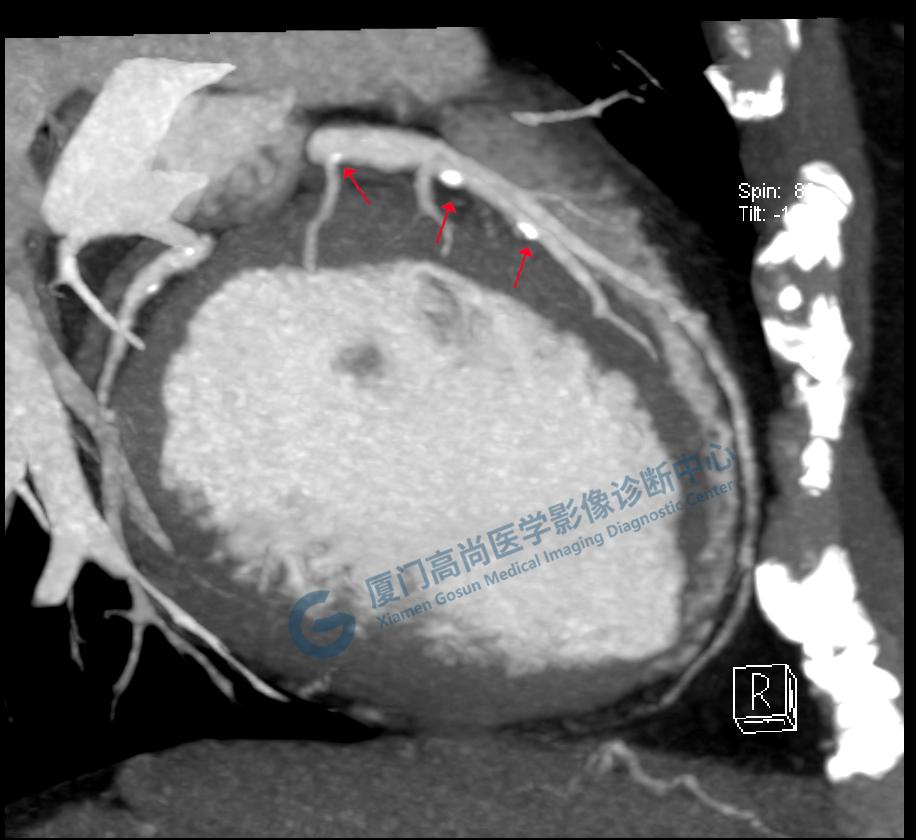

冠脈CTA圖像

回旋支

前降支

圖像所見(jiàn):左冠狀動(dòng)脈前降支,前降支近段可見(jiàn)局部鈣化斑塊,管腔狹窄約5%,左側(cè)冠狀動(dòng)脈對(duì)角支可見(jiàn)鈣化斑塊,管腔狹窄約20%-30%。

左冠狀動(dòng)脈回旋支,近段可見(jiàn)局部鈣化斑塊,管腔狹窄約5%-10%。

影像診斷:CAD-RADS分級(jí):2(25%-49%),輕度狹窄。